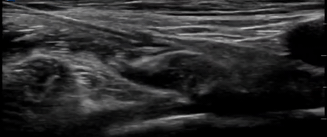

Image 1- Sono-Anatomy of the Performed Block

• Ultrasound-guided Right Femoral Nerve Block

• A - Fascia Iliaca

B - Femoral Nerve

C - Femoral Artery

D - Fascia Lata

Place the linear transducer along the inguinal crease as shown below. Try to visualise the Femoral Vein which is the medial most vessel, Femoral Artery which is lateral to the Vein and the Femoral Nerve that looks like a triangular hyper-echoic bunch of Grapes.

Clip 2 - Sono-Anatomy of the Performed Block with Annotations (FA- Femoral Artery)